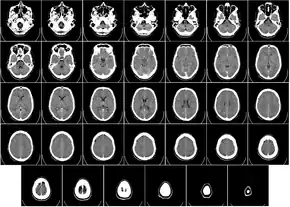

Head

CT scanning of the head is typically used to detect infarction (stroke), tumors, calcifications, haemorrhage, and bone trauma.[32] Of the above, hypodense (dark) structures can indicate edema and infarction, hyperdense (bright) structures indicate calcifications and haemorrhage and bone trauma can be seen as disjunction in bone windows. Tumors can be detected by the swelling and anatomical distortion they cause, or by surrounding edema. CT scanning of the head is also used in CT-guided stereotactic surgery and radiosurgery for treatment of intracranial tumors, arteriovenous malformations, and other surgically treatable conditions using a device known as the N-localizer.[33][34][35][36][37][38]

Two-dimensional CT images are conventionally rendered so that the view is as though looking up at it from the patient's feet.[97] Hence, the left side of the image is to the patient's right and vice versa, while anterior in the image also is the patient's anterior and vice versa. This left-right interchange corresponds to the view that physicians generally have in reality when positioned in front of patients.[98]

Water has an attenuation of 0 Hounsfield units (HU), while air is −1,000 HU, cancellous bone is typically +400 HU, and cranial bone can reach 2,000 HU or more (os temporale) and can cause artifacts. The attenuation of metallic implants depends on the atomic number of the element used: Titanium usually has an amount of +1000 HU, iron steel can completely extinguish the X-ray and is, therefore, responsible for well-known line-artifacts in computed tomograms. Artifacts are caused by abrupt transitions between low- and high-density materials, which results in data values that exceed the dynamic range of the processing electronics. Two-dimensional CT images are conventionally rendered so that the view is as though looking up at it from the patient's feet.[97] Hence, the left side of the image is to the patient's right and vice versa, while anterior in the image also is the patient's anterior and vice versa. This left-right interchange corresponds to the view that physicians generally have in reality when positioned in front of patients.